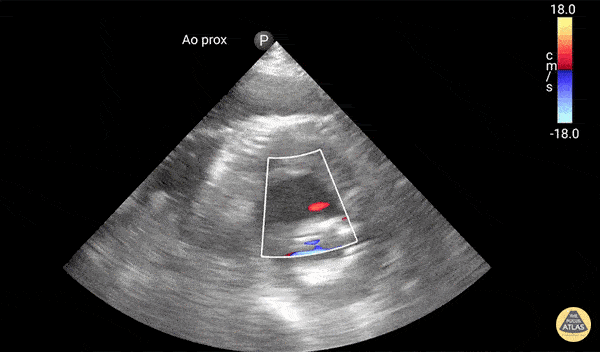

Active extravasation through endograft into false lumen. Known chronic endoleak, but CT 30 minutes prior to this study showed no active extravasation or impending rupture. Keep an open mind when reassessing your patients, and try not to anchor too much on prior results or others' opinions! Dr. Elias Jaffa